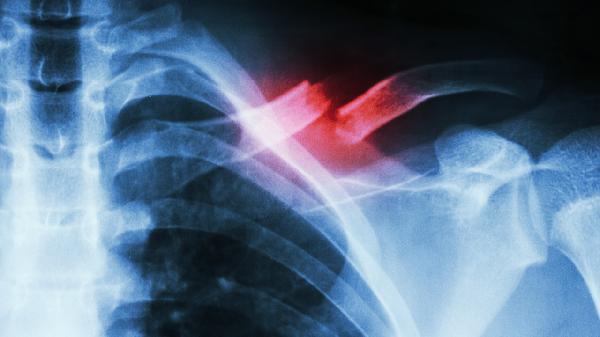

CT检查能清晰显示骨瘤的钙化程度和范围,MRI有助于评估周围软组织受累情况。典型良性骨瘤呈象牙样高密度影,若出现溶骨性破坏或周围浸润生长需警惕恶变。